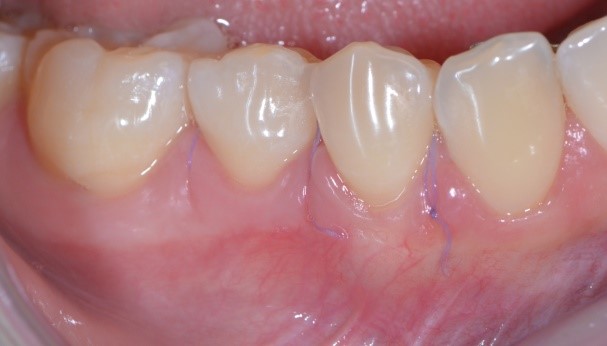

C’è un trucchetto di mezzo però. Devo confessarti che ho usato Photoshop, ma non per cambiare lo stato di salute dei tessuti (non saprei neanche come fare in verità!!) guarda qui cos’ho fatto…

Ho semplicemente cancellato via i punti di sutura. Sì perché quello è proprio l’aspetto della guarigione a 10 giorni di un lembo a spostamento coronale multiplo con innesto di connettivo prelevato dal palato! Concorderai con me che è un intervento abbastanza “aggressivo”. Si deve scollare un lembo a spessore misto, sezionale le fibre muscolari, spostare coronalmente il lembo, prendere un pezzo di “gengiva” dal palato (qui di solito i pazienti rabbrividiscono) e ficcarla sotto il lembo.

Vediamo il caso iniziale. Francesca presentava recessioni multiple con accentuata ipersensibilità dentinale.

Perché, secondo te, Francesca ha accettato di farsi tagliuzzare in 2 punti per risolvere questo problema? Te lo spiego io: perché io sapevo di poterle dare questa guarigione a 10 giorni